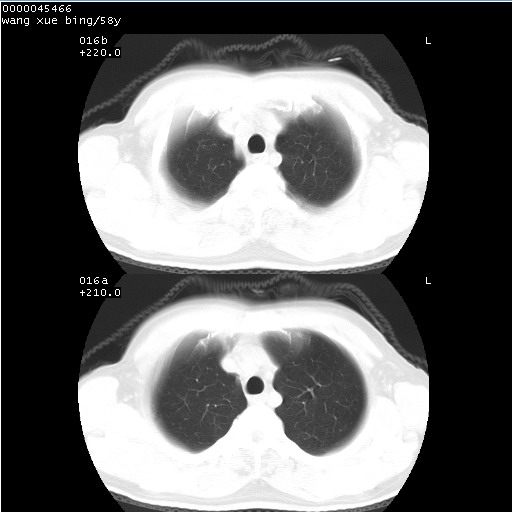

患者 男,58岁。咳嗽、咯血3月余。

胸部ct轴位平扫(层厚10mm,螺距1.5,重建间隔10mm),图像如下:

右肺下叶周围型肺癌伴空洞形成!征象比较明显!分叶、毛刺、胸膜凹陷征、厚壁空洞,壁结节!

空洞壁厚,不规则,其内可见壁结节,周围可见毛刺及阻塞性炎变,多考虑癌性病变.

支持癌性空洞并远端阻塞性炎症